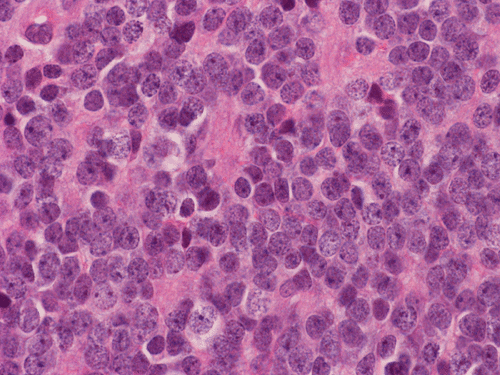

Pathology of the Case: The tumor is composed of neoplastic small blue cells on the cytologic preparation (Pancel C and D) with only minimal amount of cytoplasm. On frozen section (Panel E and F), the tumor cells are packed in solid sheets without specific pattern of arrangement. On permanent sections, the tumor again is composed of solid sheets of small blue cell tumors with rather monotonous nuclei (Panel G and H). In some areas, there is some small neuropil islands (Panel I). No distinct perivascular coronary arrangement is noted.  (Panel J). There is a moderate labeling index on Ki67 (Panel K). The tumor cells are strongly positive for neurofilament proteins (Panel L). Some large stellate, cells positive for glial fibrillary acidic protein (GFAP) are also present and these cells may represent reactive astrocytes (Panel M).

In essence, PPTID is composed of diffuse sheets or large lobules of  uniform cells with mild to moderate nuclear atypia and low to moderate levels of mitotic activity.  Differentiation of grade II and III tumors can be made based upon a combination of mitotic activity levels and neurofilament protein immunoreactivity. Rare mixed tumors exhibiting characteristic elements of both pineocytoma and pineoblastoma have also been classified as PPTID, albeit somewhat controversially. The tumor classification of PPTID originated in 1993 with the work of Schild, et al. reviewing data on 30 patients with pineal parenchymal tumors diagnosed between 1939 and 1991. Of the 30 pineal parenchymal tumors, four were sub-classified as PPTID by Schild and his colleagues 9.

PPTID has a histopathologic picture of a small blue cell tumor. However, the degree of pleomorphism is not as high as pineoblastoma or medulloblastoma. Particularly for the one with better differentiation, the cells would have overall features suggestive of lymphocytes. This would further suggest germinomas as they are associated with a substantial amount of lymphocytes. Search for large germinoma cells would be the diagnostic clue to distinguish these two categories. Histological distinction of PPTID with teratomas, yolk sac tumors, embryonal cell carcinomas, and choriocarcioma components in germ cell tumors is relatively straightly forward. The table below provides comparison of different types of pineal parenchymal tumors.